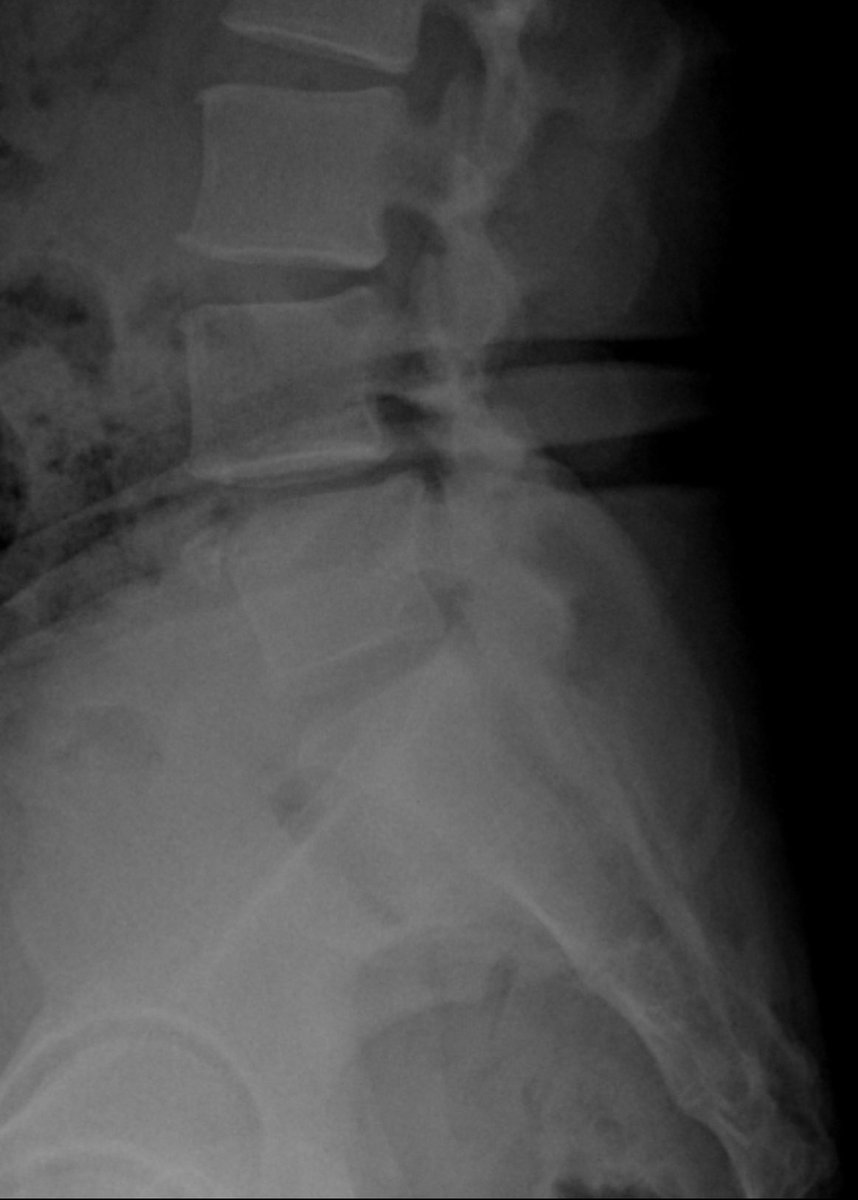

Case I performed recently.